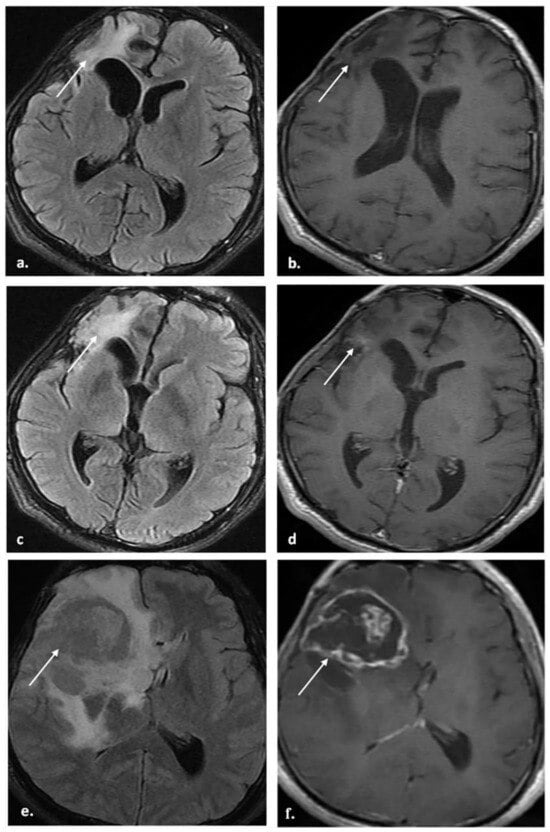

| BT-RADS-3c | Worsening favors TP. Clinically worsening. | Significant increase (>25%) in enhancing component, FLAIR component, mass effect, or definite new lesion compared with prior MRI. | Change in management vs. decreased time interval of follow-up. |

| BT-RADS-4 | Worsening, highly suspicious for TP. Clinically worsening. | Substantial increase in enhancing component, FLAIR component, mass effect, and/or multiple new lesions compared with prior MRI. | Change in management. |